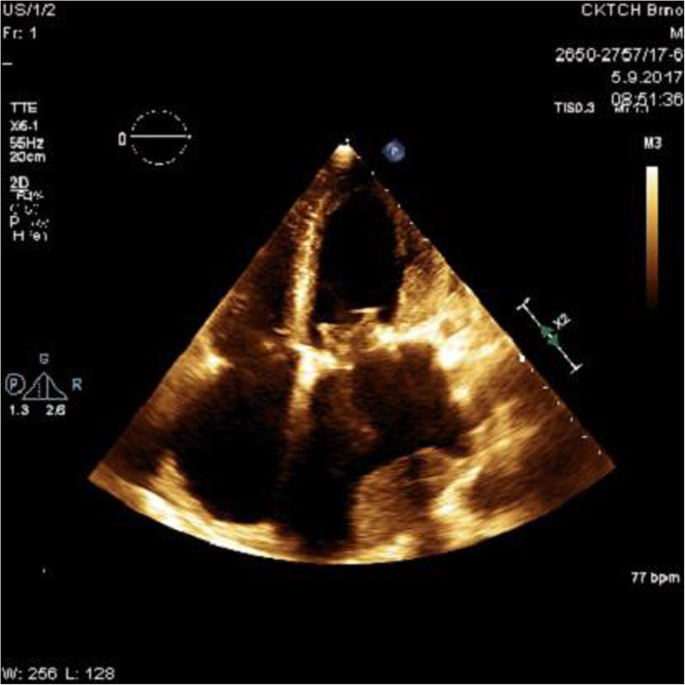

In 2017, after 8 years, he was admitted to the Cardiology Clinic. The precipitating reason for his admittance was progressive and exertional dyspnoea – New York Heart Association (NYHA) grade II-III. A transthoracic (TTE) and transoesophageal echocardiogram (TEE) revealed a giant LA sized 75x105mm, his left ventricular (LV) diastolic diameter was 60mm and the ejection fraction (EF) was 65%. Echocardiographists further described the presence of mitral annular dilatation with ruptured and flailed chordae tendinea of the prolapsed anterior leaflet, and significant mitral regurgitation with a regurgitation volume of 50ml. A supplementary finding was tricuspid regurgitation of borderline hemodynamic significance (Figure 1).